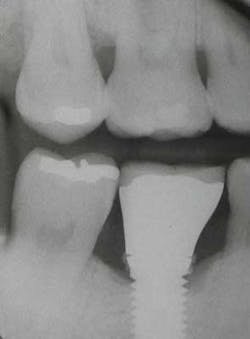

Fig. 3: After using Slimline ultrasonic, cement is removed.